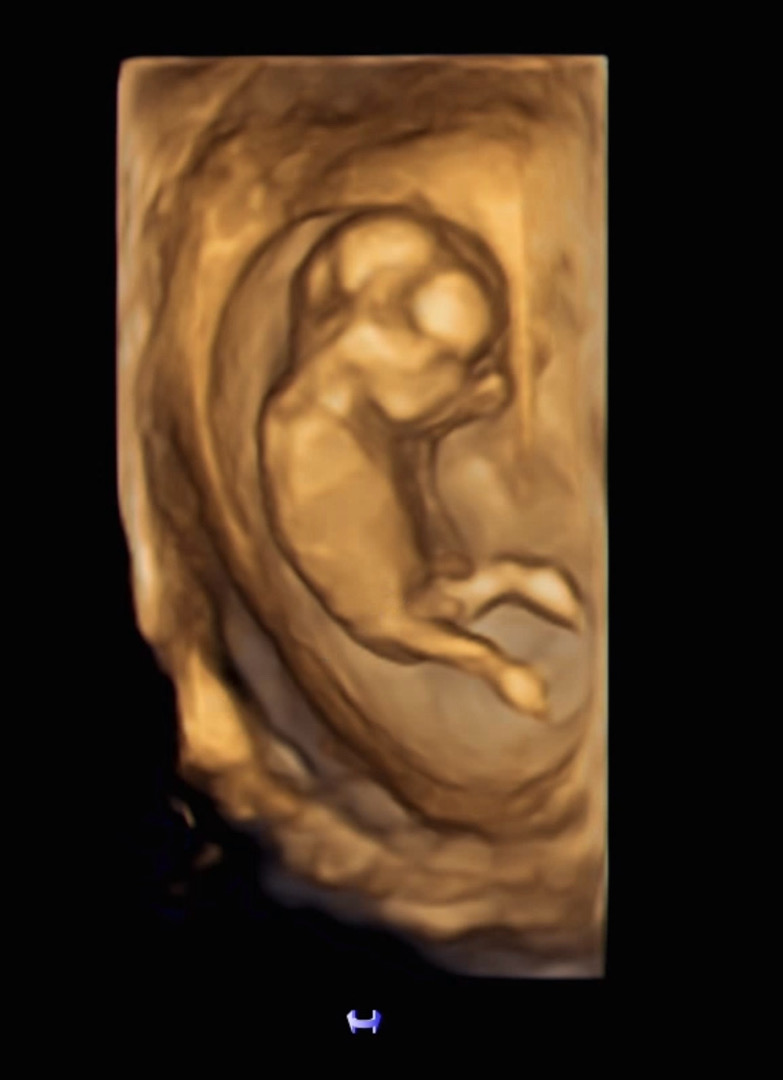

드디어 12주 기형아 검사 하고왔어요~~ 오랜만에 갔더니 꿈틀꿈틀 이제 많이 움직이더라구요!! ㅋㅋㅋ 시끄러운지 귀를 막은것 같은 모습..! 이제 사람같아요!! 일단 초음파상 목투명대는 0.05라고하네용 2주후에 결과나온다는데 어차피 정상일거라고 믿지만 괜히 떨리네요~ㅋㅋ 저 다리 사이는 아직 딸인지 아들인지 아직은 모른다구 하셔서 궁금궁금..! 각도법 보려고해도 아무리 봐듀 모르겠어서 포기했어요 ㅋㅋㅋ 아들일까요 딸일까요?!